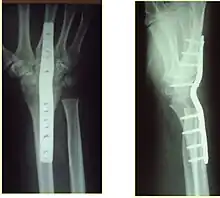

Surgery

Surgery is generally indicated for displaced or unstable fractures.[18] The techniques of surgical management include open reduction internal fixation (ORIF), external fixation, percutaneous pinning, or some combination of the above. The choice of operative treatment is often determined by the type of fracture, which can be categorized broadly into three groups: partial articular fractures, displaced articular fractures, and metaphyseal unstable extra- or minimal articular fractures.[5]

Significant advances have been made in ORIF treatments. Two newer treatments are fragment-specific fixation and fixed-angle volar plating. These attempt fixation rigid enough to allow almost immediate mobility, in an effort to minimize stiffness and improve ultimate function; no improved final outcome from early mobilization (prior to 6 weeks after surgical fixation) has been shown. Although restoration of radiocarpal alignment is thought to be of obvious importance, the exact amount of angulation, shortening, intra-articular gap/step which impact final function are not exactly known. The alignment of the DRUJ is also important, as this can be a source of a pain and loss of rotation after final healing and maximum recovery.

If the fractures are unlikely to be reduced by closed means, open reduction with internal plate fixation is preferred.[5] Although major complications (i.e. tendon injury, fracture collapse, or malunion) result in higher reoperation rates (36.5%) compared to external fixation (6%), ORIF is preferred, as this provides better stability and restoration of the volar tilt.[5][23] Following the operation, a removable splint is placed for 2 weeks, during which time patients should mobilize the wrist as tolerated.[5]